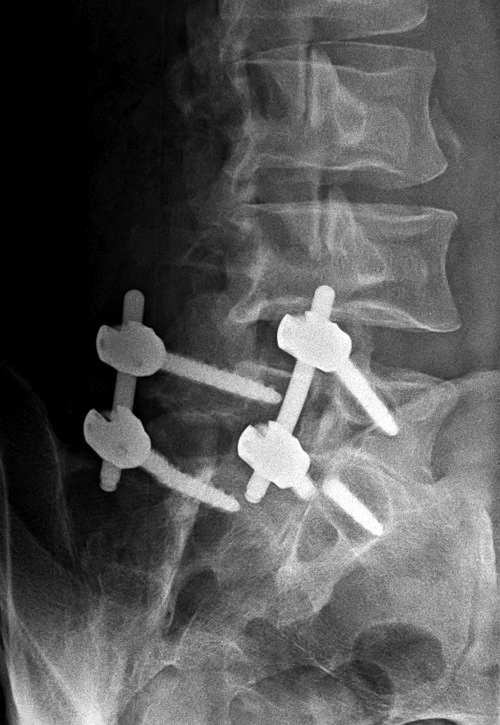

Lumbar spine bony disk strut, pedicle screws, and pedicle rods (lateral view) |

20 year-old woman with L1 vertebral body compression fracture treated with T12-L2 posterior spinal fusion using pedicle screws at T12 and L2 with connecting rods on each side. |

There are also bilateral pedicle screws and connecting rods above and below the level of the fracture. |